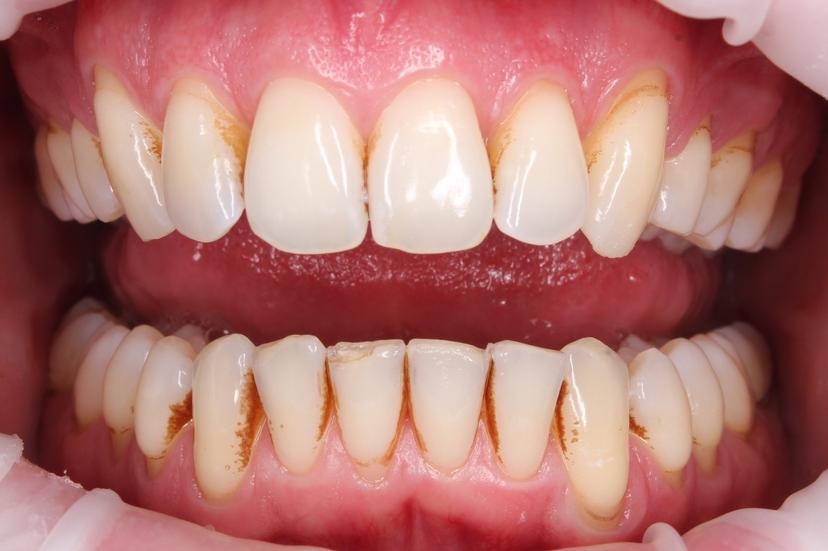

Пациент пришел с жалобами на неприятный запах изо рта и на темный налёт, который не убирается зубной щеткой.

Для снятия зубных отложений мы провели комплексную профилактическую гигиену с применениям ультразвука, AIR FLOW, щетки с пастой.

ДО: Заметны налет, пигментация и твердые зубные отложения, что придает неухоженный вид зубам.

После: Поверхность зубов очищена, восстановлен их естественный цвет, отсутствуют твердые зубные отложения и налет. Зубы выглядят здоровыми и ухоженными, а десны - свежими и более розовыми.